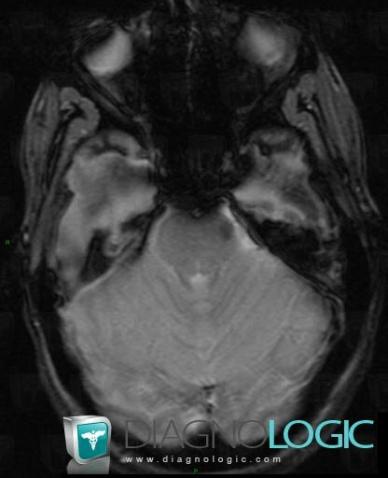

Télangiectasie capillaire, Fosse postérieure, IRM

Voici les informations spécifiques à l'image clé ci dessus:

- Diagnostic Télangiectasie capillaire, Localisation(s) Fosse postérieure, comportant les gammes Lésion infratentorielle en isosignal T2 ou FLAIR